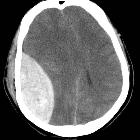

Typically lentiform (lens-shaped, biconvex, lemon-shaped) and do not cross sutures as the periosteum crosses through the suture continuous with the outer periosteal layer.

Subdural hematoma

Typically crescentic (crescent moon-shaped, concave, banana-shaped) and more extensive than EDH, with the internal margin paralleling the cortical margin of the adjacent brain. As these occur in the subdural space, they cross sutures.